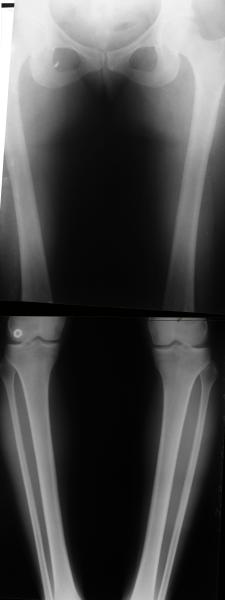

AC> Обратилась дама 25 лет. Вынуждена ходить в брюках из-за genu varum,

AC> что побудило обратиться за коррекцией.

Сейчас это модно (в смысле косметическая коррекция)... Хотя, судя по фото - в данном случае енто вполне оправдано...

Судя по снимку у девушки имеется внутренняя установка надколенников...

Как у нее с торсионным статусом? Бедро? Голень? КТ? Торсиометры? А то, куда будут

смотреть надколенники после вашей коррекции - тоже существенный

косметический момент. Или не так?

Your patient appears to have "Insquinting Knees"?

I am attaching a word doc with a 'print screen' of the program in use, showing the images being viewed and analysed

. On the right leg you can see some of the tools (from the tool bar above) applied to demonstrate a mild mech-axis varus of about 5 degrees.

On the left the bone landmarks used in the anlaysis are shown.

The data for the analysis are in the XLs sheet below, exported from the program automatically.

I have given a label of the abreviations and some normative values.

In essence she has a mild mech-axis varus of 7 degrees with some contribution from the femur (2) degrees and more from the tibia (6 degrees), none from the joint.

The analysis took about 6 mins.

Regards

Derek